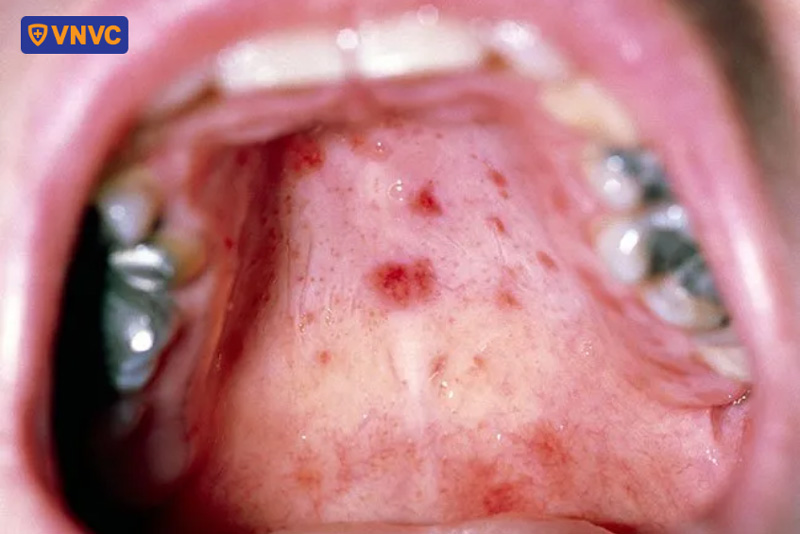

Sau các giai đoạn tiền triệu, khi bệnh đi vào giai đoạn toàn phát sẽ xuất hiện các nốt ban đỏ ở tay, chân, thậm chí ở mông trong khoảng 2 - 4 ngày. Các nốt ban nhỏ sẽ dần phát triển thành mụn nước, chứa đầy dịch trong suốt bên trong. Trong một số trường hợp, các nốt ban đỏ và mụn nước có thể phát ban phồng rộp ở bộ phận sinh dục và ở trong miệng.